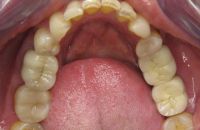

Na de behandeling

De zes voortanden en twee kleine kiezen in de bovenkaak zijn opgebouwd met composiet. Hierdoor zijn ze verlengd en volledig ingepakt met composiet, zodat ze niet meer zo snel kunnen breken.

De afgebroken kies in de onderkaak is verwijderd en in het hiaat zijn twee implantaten geplaatst met kronen.

Uiteindelijk heeft meneer ook een beschermende nightguard gekregen om ervoor te zorgen dat het knarsen geen schade kan geven aan zijn gebit.